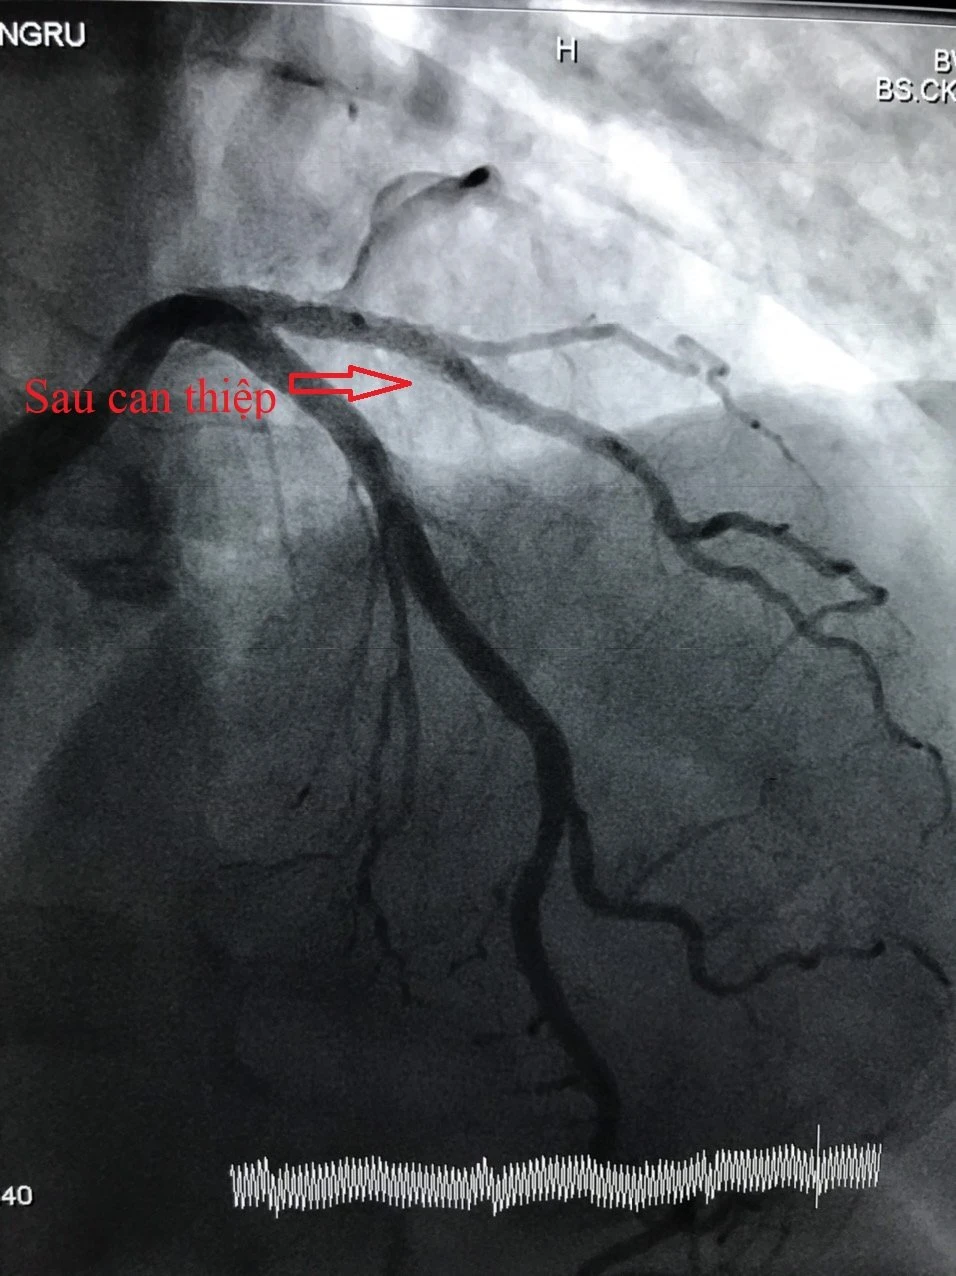

Hình ảnh tổn thương mạch vành trước và sau can thiệp. Ảnh: BVCC 1 Hình ảnh tổn thương mạch vành trước và sau can thiệp. Ảnh: BVCC 2

Hình ảnh tổn thương mạch vành trước và sau can thiệp. Ảnh: BVCC

Qua khám và tiến hành xét nghiệm bác sĩ xác định bệnh nhân bị nhồi máu cơ tim cấp, động mạch liên thất trước (LAD) bị thâm nhiễm, hẹp 80%-90% nhánh chéo 1 và có chỉ định can thiệp mạch vành cấp cứu. Các bác sĩ đã tiến hành can thiệp mạch vành cho bệnh nhân bằng cách nong bóng và đặt stent phủ thuốc với thời gian 30 phút.